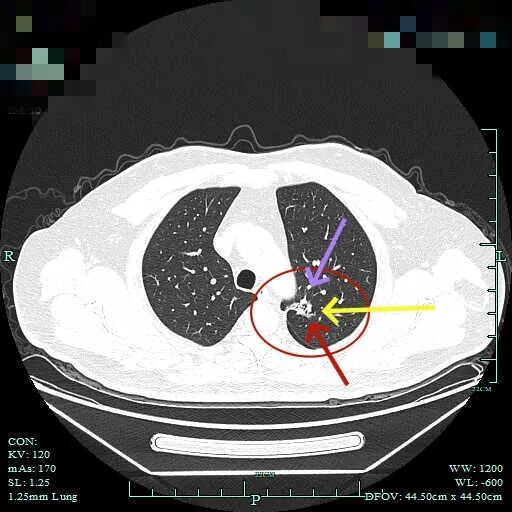

再看2025年10月时该市级中医院的影像:

病灶到了2025年10月范围略有扩大,但不太厉害,不过密度明显增加,表面不平,整体轮廓与瘤肺边界清楚,灶内有条状密度增高,靠右侧向叶间裂处延伸,已经搭上胸膜了。这基本上就是浸润性癌的了!